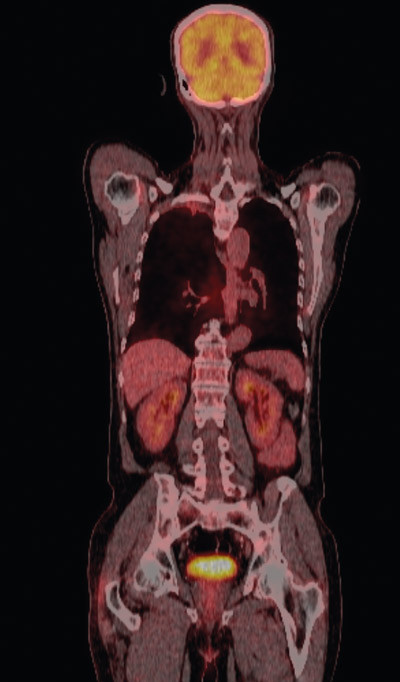

Fire uker etter avsluttet behandling ble pasienten reinnlagt til operativ behandling med kurativ intensjon. Ny MR collum/thorax viste fortsatt sannsynlig innvekst i 2. og 3. høyre costa samt mulig tumoraffeksjon av Th 2. Det var ikke tegn til affeksjon av plexus brachialis. CT viste at tumor hadde skrumpet (fig 2c, d). Det ble også utført PET-CT (fig 4). Denne var uegnet til vurdering av lokale forhold pga. pasientens nylig gjennomgåtte strålebehandling, men viste ingen tegn til viabelt tumorvev i thoraxveggen eller malignitet andre steder i kroppen. Basert på PET-CT-funnene ble pasienten etter tverrfaglig vurdering bedømt som operabel, og det ble gjennomført lobektomi av høyre overlapp.

For å kunne vurdere operabiliteten på et best mulig grunnlag bør evaluering etter kjemoradioterapi inkludere både CT og MR thorax, og helst også PET-CT-undersøkelse, som har vist høyere sensitivitet og spesifisitet enn CT-undersøkelse ved stadieinndeling og deteksjon av ekstrakraniale fjernmetastaser hos pasienter med lungekreft av ikke-småcellet type (8). Dersom pasienten er operabel, bør inngrepet foretas innen fire uker. Om operasjon ikke er aktuelt, anbefales videreføring av stråleterapi til 66 Gy, ev. i kombinasjon med ytterligere en PV-kur. Ved lokal progrediering eller fjernmetastaser bør annen kjemoterapi eller palliativ bestråling av metastasene vurderes.